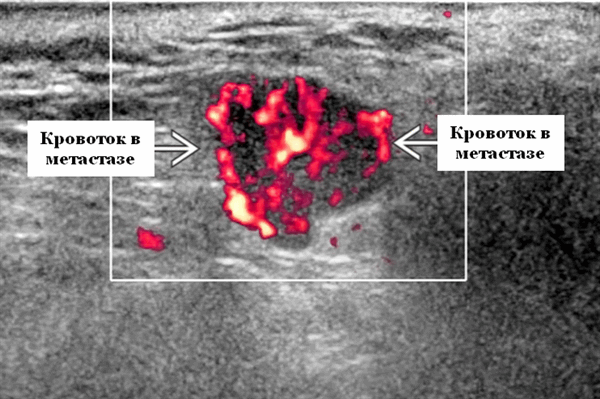

- Отмечается внутренняя васкуляризация на цветном доплеровском исследовании.

- Цветной допплер. Внутриузловая васкуляризация от умеренной до выраженной

Цветной допплер. Узловая НХЛ. Выраженная центральная или внутриузловая гиперваскуляризация. Паренхима при неходжкинской лимфоме более диффузная железистая гиперваскуляризация. Васкуляризация от умеренной до выраженной в плохо очерченных образованиях.

- Интранодулярный кровоток хаотичный / дезорганизованный или преимущественно периферический

Визуализация. Общие особенности. Само по себе ультразвуковое сканирование метастазов в околоушные лимфоузлы неспецифична. Одиночные или множественные околоушные образования. Хорошо выраженный или плохо выраженный лимфоузел (экстранодальное распространение), однородный или неоднородный с внутренним некрозом. На УЗИ с ЦДК внутриузловая васкуляризация или усиление кровотока. Патология связана с известным первичным раком, часто в прилегающей коже или региональной области головы и шеи. Околоушные и перипаротидные узлы: узловая станция 1-го порядка при плоскоклеточной карциноме кожи (ПКК) и меланоме латеральной части волосистой части головы, ушной раковины / наружного слухового прохода и передней части лица

Энергетический допплер. Внутриочаговая васкуляризация. Хаотический / дезорганизованный или преимущественно периферический кровоток